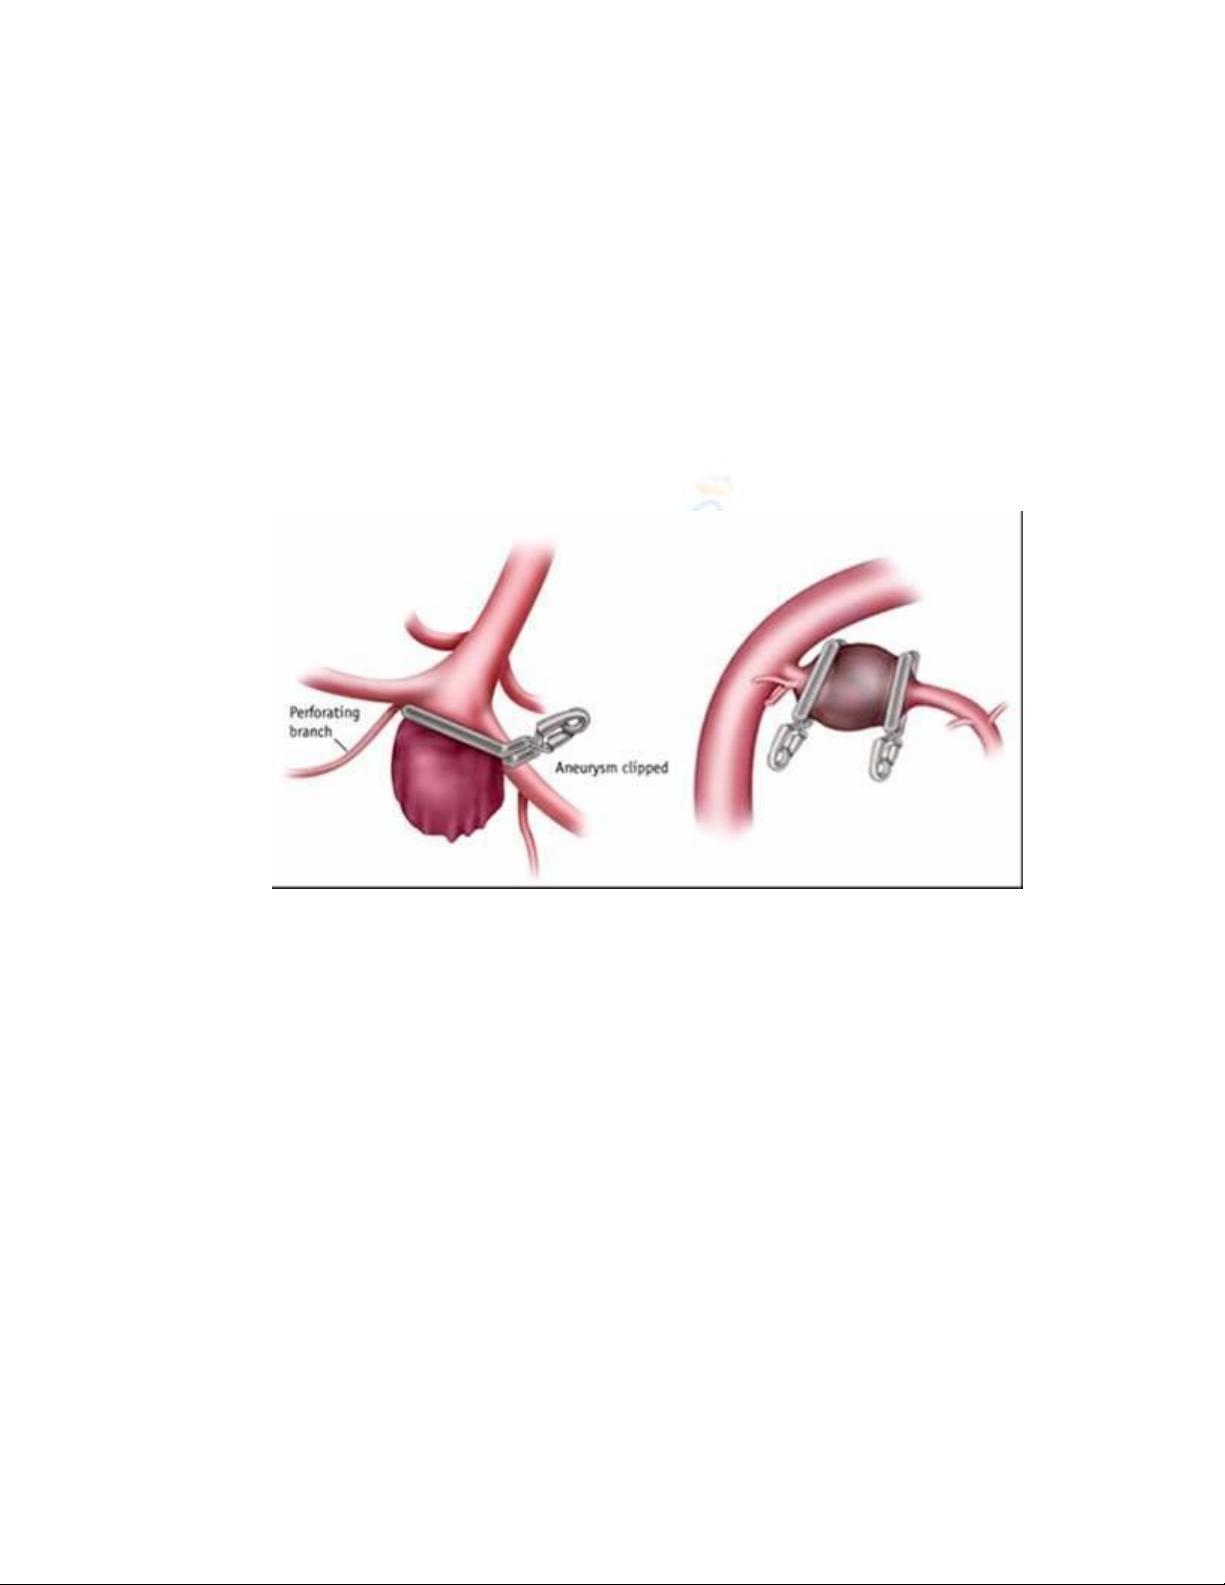

a. Kẹp (clipping): Bác sĩ phẫu thuật thần kinh mổ sọ não hở, xác định vị trí

mạch máu tổn thương và đặt một clip (kẹp mạch máu) ngang qua túi phình. Việc

làm này sẽ ngăn máu không chảy vào túi phình nữa. Túi phình sẽ ngừng tăng

trưởng và chấm dứt nguy cơ nứt vỡ gây xuất huyết.